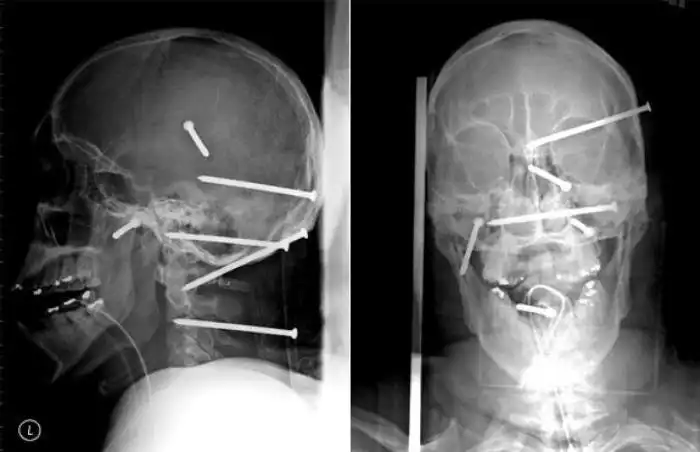

Необычные предметы в теле людей на рентгеновских снимках

На рентгеновских снимках людей порой можно обнаружить самые необычные предметы, которые находятся в их теле.